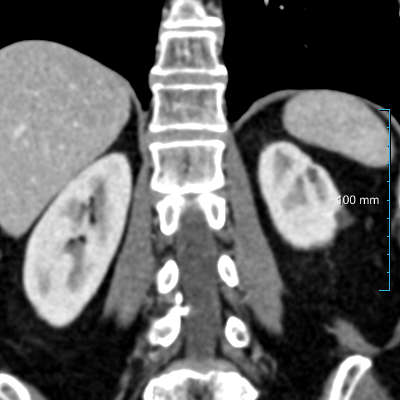

Refer to caption

(a) Patients without kidney abnormalities.

(b) Patients with kidney abnormalities.

Figure 3: Four examples of CT scans from the training set (dataset A) showing coronal sections with annotations in format 2 (see Figure 2(c)) where yellow and red overlays represent annotations of the parenchyma and kidney abnormalities, respectively. Note that all the patients have anomalies in the body (green arrows in the body), and both cases of (b) have only one kidney and contain kidney abnormalities. All the slices have a window center of 60 HU and a window width of 360 HU.

Samples of CT scans from patients included in this study can be seen in Figure 3. While Figure 3(a) depicts patients without kidney abnormalities, it highlights the presence of abnormalities in other parts of the body, such as liver tumors. Figure 3(b) shows patients with kidney abnormalities, as well as other abnormalities in the body, such as nephrectomy and collapsed lung.